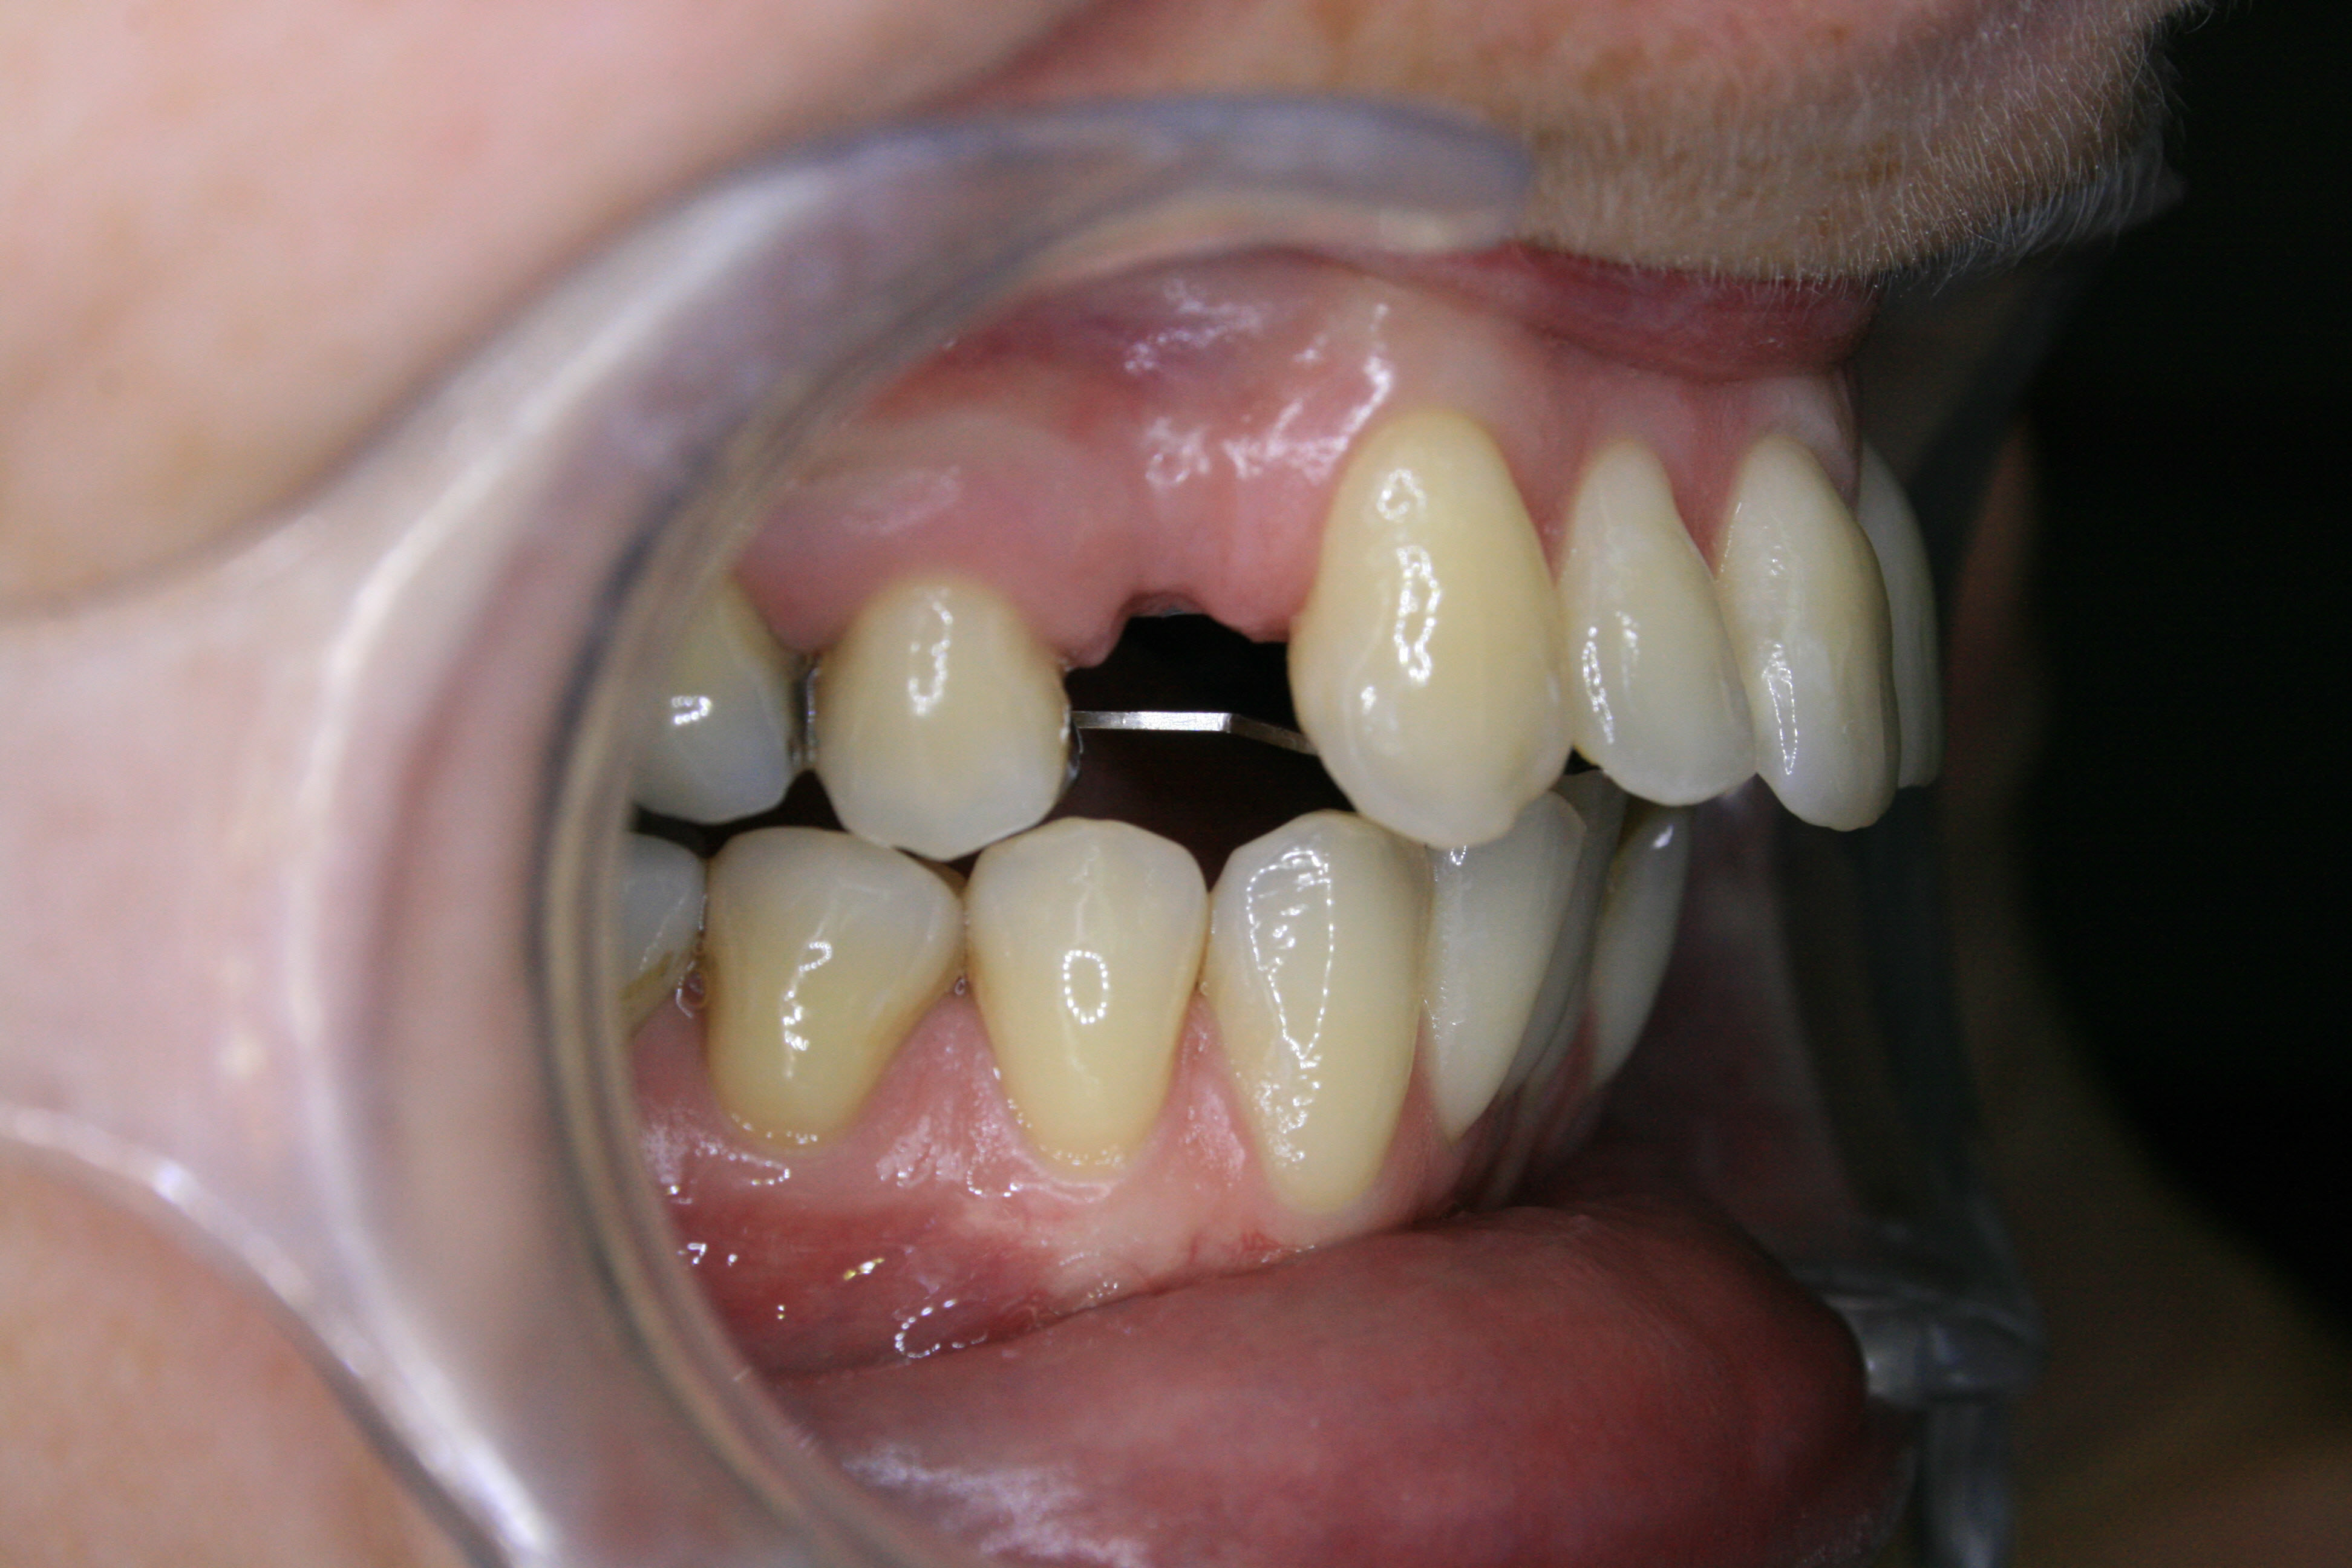

Vor der Behandlung

Bei dieser Patientin standen die oberen Schneidezähne so weit vor, daß sie auf der Unterlippe aufstanden, und der Mund nicht richtig geschlossen werden konnte. Zu der Fehlstellung trugen sowohl die stark nach vorne gekippten oberen Schneidezähne, als auch der zu kurze, zurückliegende Unterkiefer bei. Die Patientin litt sehr unter ihrer Fehlstellung, hatte aber zu große Bedenken, sich den Unterkiefer chirurgisch nach vorne setzen zu lassen. Um obere und untere Schneidezähne dennoch in Kontakt zu bringen, wurden im Oberkiefer zwei kleine Backenzähne entfernt. Die entstandenen Lücken wurden dazu genutzt, die oberen Frontzähne zurückzuziehen. Dabei mußte besonderes Augenmerk auf die folgenden Punkte gerichtet werden: